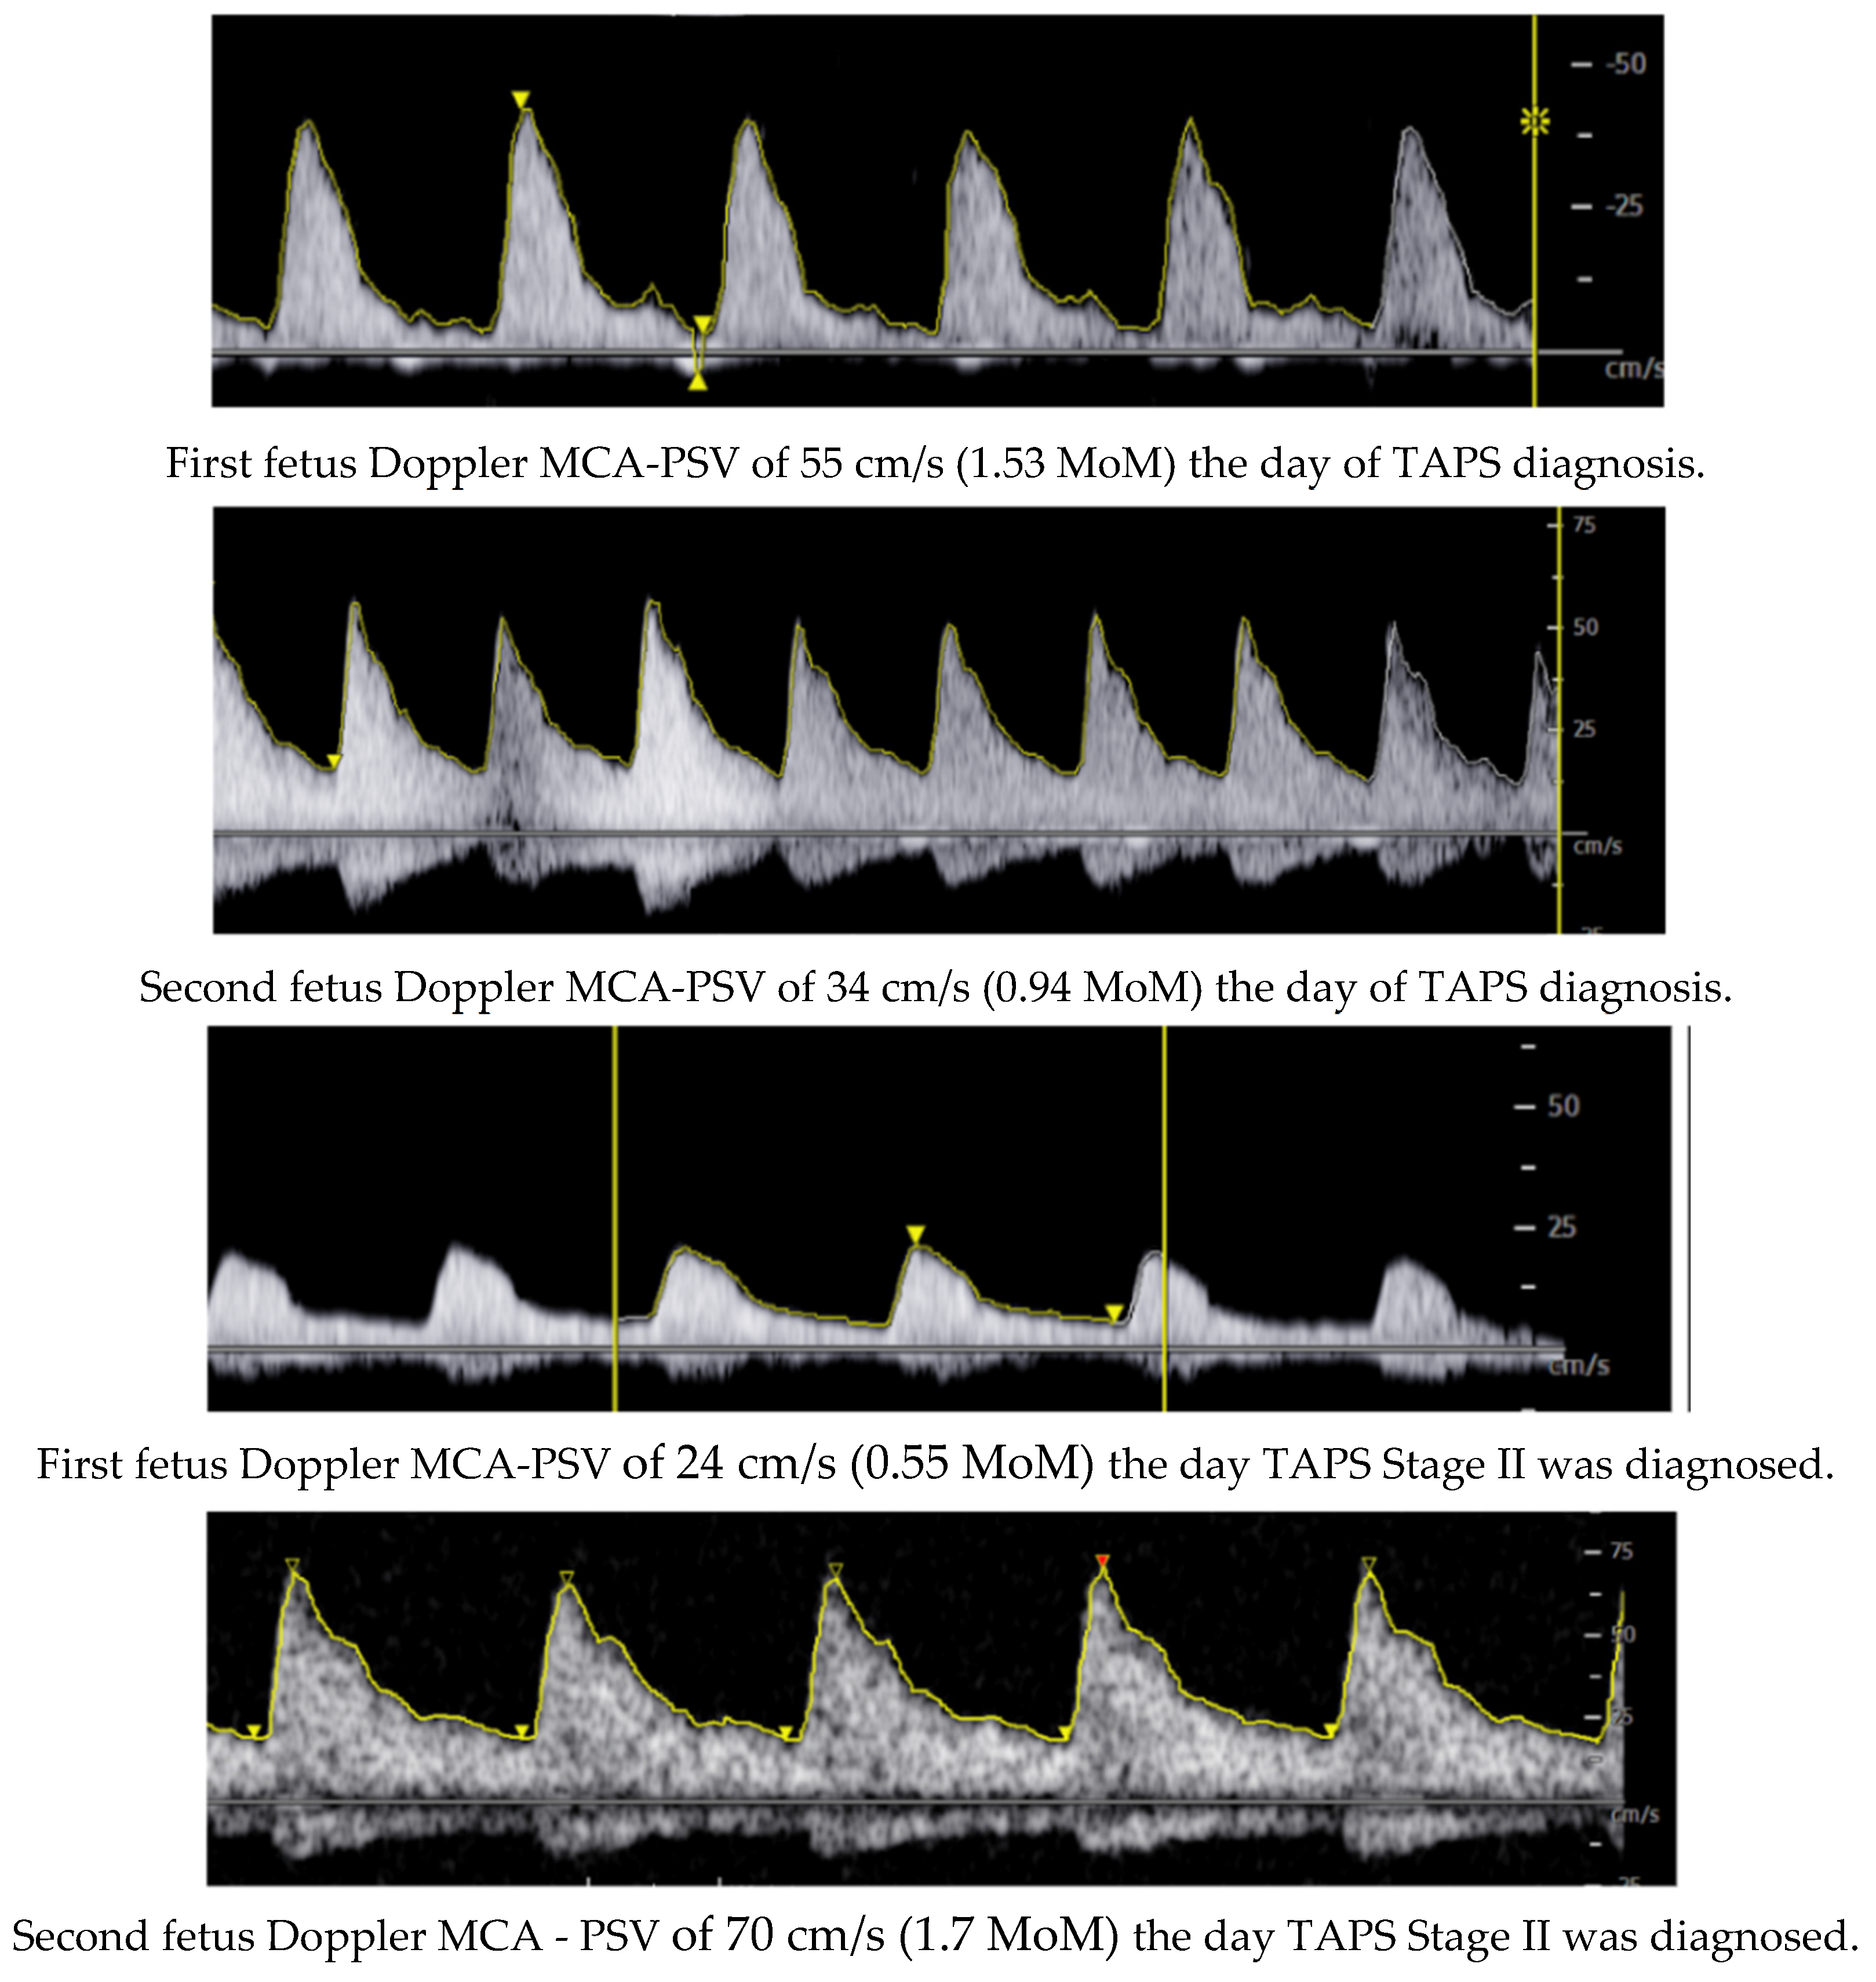

During her stay, a control ultrasound at week 27 + 5 revealed the following: the first fetus had an estimated fetal weight (EFW) of 1073 g (27th percentile), a PSV of 55 cm/s (1.53 MoM), a normal UA PI, a visible bladder, and normal AFV; the second fetus had an EFW of 1221 g (74th percentile), a PSV of 34 cm/s (0.94 MoM), a normal UA PI, a visible bladder, and normal AFV. The placenta was located on the posterior wall with discordant echogenicity (Figure 1). Given the findings and the suspicion of TAPS, the case was presented to the multidisciplinary perinatology committee, and it was decided to follow up with ultrasound monitoring twice a week for evaluation.

Figure 1. Placenta discordant echogenicity.

In addition, other ultrasonographic characteristics can support the diagnosis. One of these is discordant placental echogenicity: the placenta corresponding to the donor fetus is thicker and more echogenic compared to that of the recipient fetus. Another described finding is the “Starry sky liver”, where hyperechoic points (corresponding to portal venules) are seen against a background of decreased echogenicity in the liver parenchyma of the recipient twin. Finally, cardiac compromise, Doppler alterations, and fetal hydrops may be observed in the later stages of TAPS [4,5,8,9].